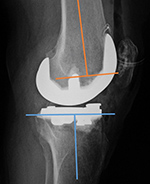

| Total Knee arthroplasty (TKA) Evaluation |

| 67 year-old woman. Postoperative images of a Biomet XPA Bicruciate Preserving TKA. Same patient as above. On the AP view (left image) the femorotibial angle is the intersection between the femoral anatomic axis (blue line) and the tibial anatomic axis (orange line). The femoral component should be centered along the femoral anatomic axis, and the tibial component should be perpendicular to the tibial anatomic axis. The femorotibilal angle should be 4-7° valgus. On the lateral view (right image) the femoral component should be roughly perpendicular to the femoral anatomic axis (orange line), and the tibial component should be perpendicular to the tibial anatomic axis (blue line) or have slight flexion (3°–6°) [posteriorly sloped]. |